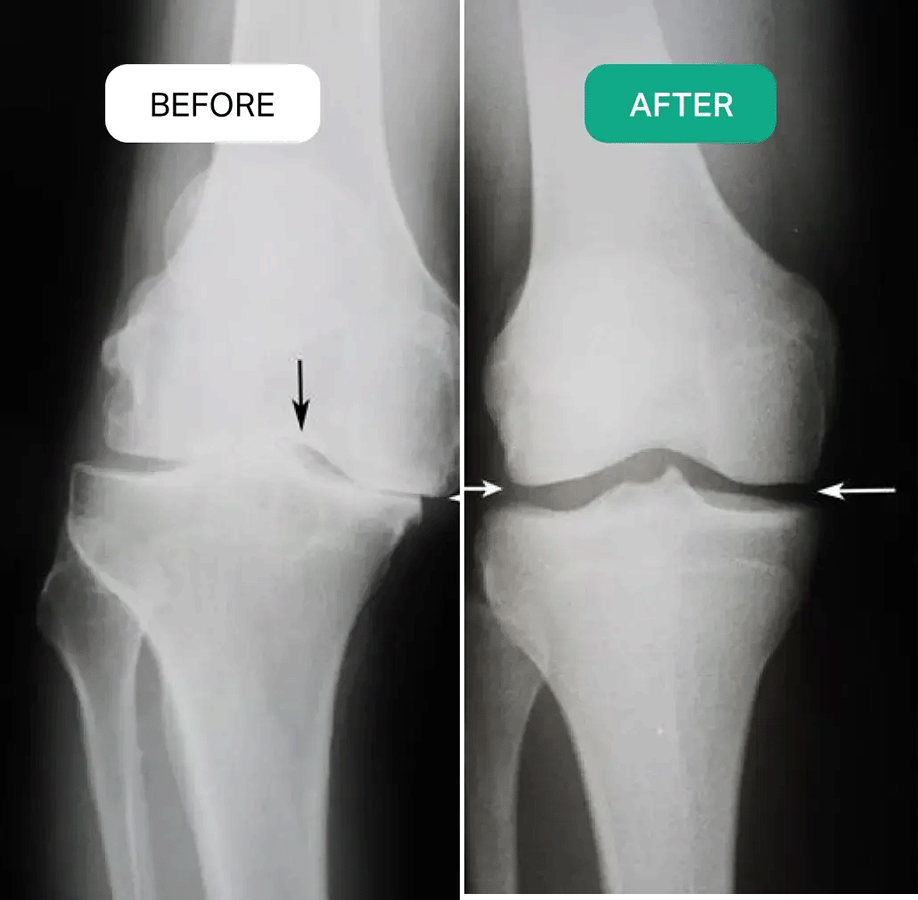

Both my knees are bone-on-bone, and I was almost completely immobile for the last 6 years. I started using the RejuvaKnee massager and it's been a miracle. I've used it twice a day for 15 minutes and it just gets rid of the pain. My mobility has dramatically improved and the constant swelling and inflammation is gone. I can't thank you enough...